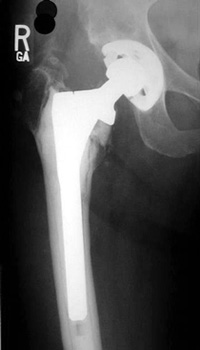

LOOSENING

No prior studies available. Abnormally widened interfaces surrounding entire cement mantle of femoral component, consistent with loosening.